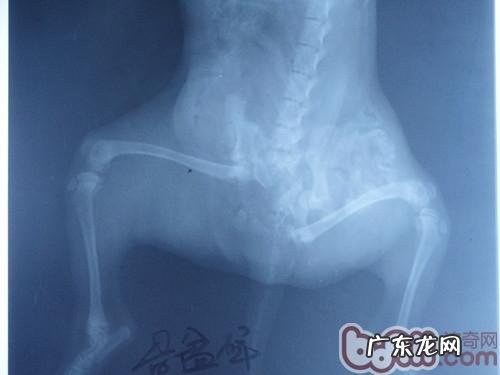

它是一例被辗压的盆骨骨裂的流浪犬,到医院门诊早已奄奄一息,查验全过程中发觉腹部器官遭受比较严重危害,极其缺铁性贫血,呼吸不畅,结膜炎惨白,腹腔彭大,人体体温早已检验不上,心率极低,救治全过程中身亡 。

盆骨骨裂的流浪犬